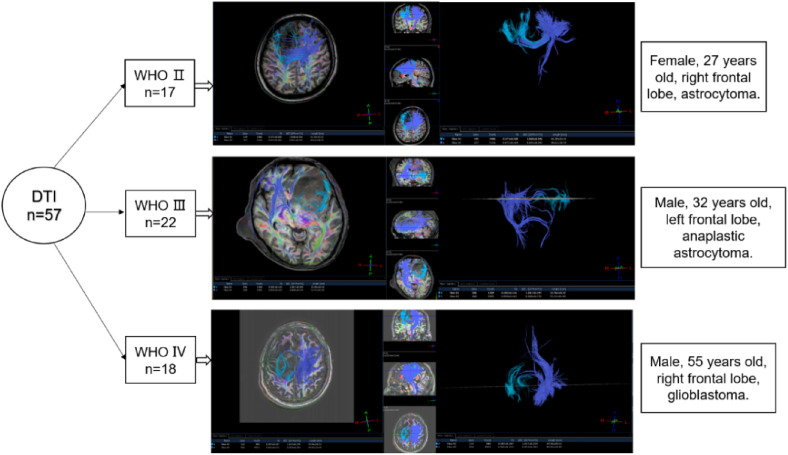

Objective: To investigate the performance of diffusion-tensor imaging (DTI) and hydrogen proton magnetic resonance spectroscopy (1H-MRS) parameters in predicting the immunohistochemistry (IHC) biomarkers of glioma.

Methods: Patients with glioma confirmed by pathology from March 2015 to September 2019 were analyzed, the preoperative DTI and 1H-MRS images were collected, apparent diffusion coefficient (ADC) and fractional anisotropy (FA), in the lesion area were measured, the relative values relative ADC (rADC) and relative FA (rFA) were obtained by the ratio of them in the lesion area to the contralateral normal area. The peak of each metabolite in the lesion area of 1H-MRS image: N-acetylaspartate (NAA), choline (Cho), and creatine (Cr), and metabolite ratio: NAA/Cho, NAA/(Cho + Cr) were selected and calculated. The preoperative IHC data were collected including CD34, Ki-67, p53, S-100, syn, vimentin, NeuN, Nestin, and glial fibrillary acidic protein.

Results: One predicting parameter of DTI was screened, the rADC of the Ki-67 positive group was lower than that of the negative group. Two parameters of 1H-MRS were found to have significant reference values for glioma grades, the NAA and Cr decreased as the grade of glioma increased, moreover, Ki-67 Li was negatively correlated with NAA and Cr.

Conclusion: NAA and Cr have potential application value in predicting glioma grades and tumor proliferation activity. Only rADC has predictive value for Ki-67 expression among DTI parameters.